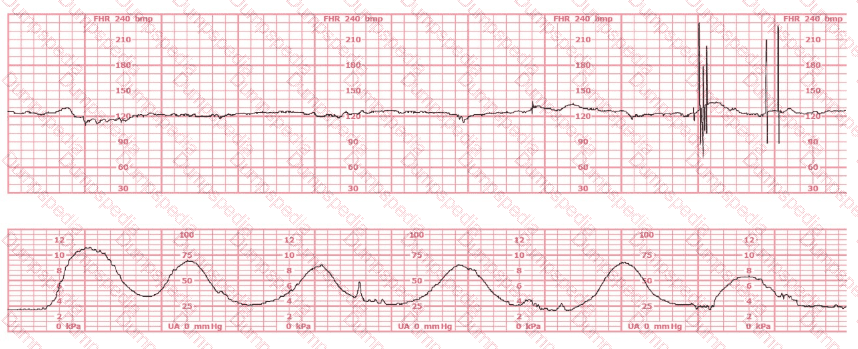

A woman at 41-weeks gestation is being induced. She is 2 cm dilated and is on oxytocin at 8 milliunits/minute. Based on the fetal heart rate tracing shown, the best initial response is to: